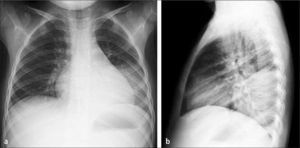

En el análisis de las Rx de tórax de los niños es importante observar cuidadosamente los hilios, el área retrocardíaca y las bases pulmonares (proyectadas retrodiafragmáticas en placas frontales), que corresponden a sitios en que se localizan las neumonías denominadas escondidas (Figura 4).